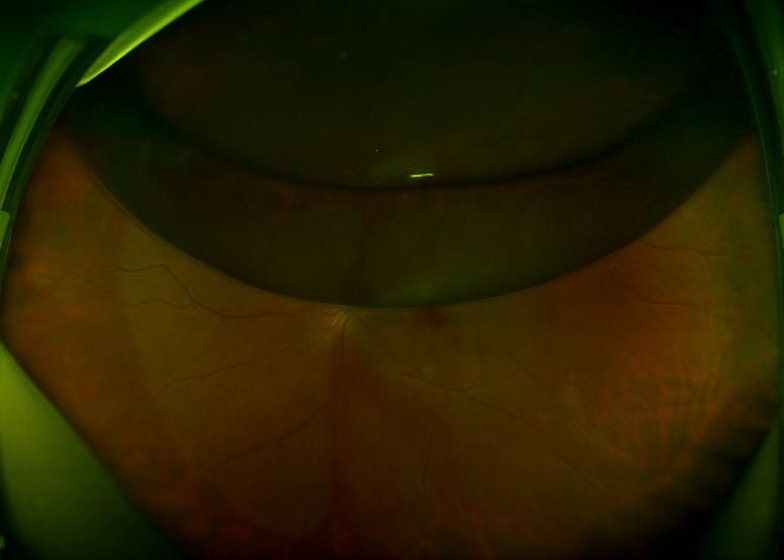

针对黄斑大出血,中国中医科学院眼科医院眼四科开展微创玻切联合视网膜注药手术,手术时间短,恢复快,疗效显著。先完成微创玻璃体切割手术后,使用41 G针头进行黄斑区网膜下注射TPA(组织纤溶酶)0.1 mL,剂量25 mg至50 mg。TPA可将网膜下出血液化,通过气体顶压离开黄斑区并吸收,有助于黄斑区结构恢复以及视力提高,挽救患者视力,尤其是黄斑出血两周内效果较好,急性出血立即网膜下注射TPA可以有效液化出血,帮助患者重见光明。

典型病例:患者,男,75岁,右眼视力下降五天,视力:指数/30 CM,诊断:黄斑变性.

手术方案:微创玻切加网膜下注药,患者术后第三天视力:0.2。

图1

图2